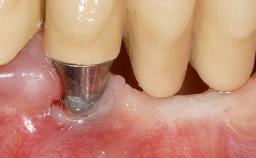

A 30-year-old woman was referred by her general dentist for evaluation of an esthetic complication related to previous implant treatment for congenitally missing maxillary lateral incisors. The patient’s chief complaint was the inadequate esthetic appearance of her smile. The case demonstrates the use of a combined approach to achieve optimal results. Two different flap designs - a tunnel technique and a coronally advanced flap - are employed based on the surgical objectives for the affected site.

Soft Tissue Grafting Yes

Abutment Type Standard